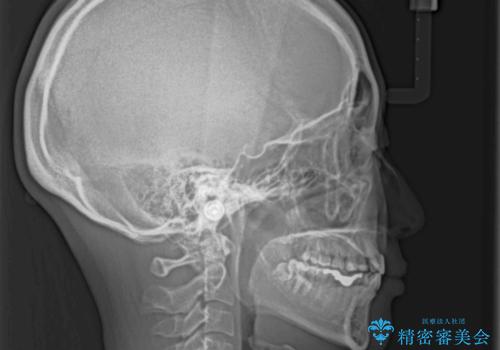

- 残存した乳歯や歯の欠損、歯並びを気にして来院された患者様です。

乳歯を残した状態は予後がよくないこと、矯正治療と補綴治療を総合的に進めていきたいとのことで、インビザラインによる矯正治療とインプラント補綴治療を並行して進めていくこととしました。